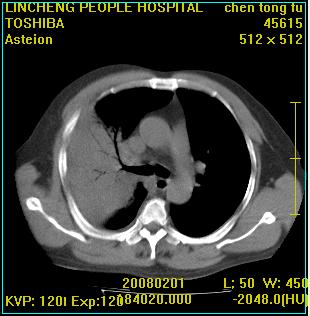

患者,男性,62岁。主因头晕,发热,咳嗽6天,高热达39度,esr19mm/h,wbc 3.9×10 9/l

大叶性肺炎并胸膜炎

右肺大叶性肺炎,胸腔积液。建议痰检。

实变区见空气支气管征,支气管通畅,考虑为大叶性肺炎,右侧少量胸水

1)考虑为:右肺感染性病变。建议:抗炎治疗复查。2)右侧少量胸腔积液。

考虑为右肺大叶性肺炎,胸腔积液,建议必要时纤维支气管镜检查,以排除肿瘤性病变。

右肺炎症并右侧胸腔少量积液。

考虑为右肺大叶性肺炎伴少量胸腔积液,建议复查,如病变不吸收或吸收不明显,建议纤维支气管镜检查,除外细支气管肺泡癌的可能。

右侧大叶性肺炎,右侧少量胸腔积液.